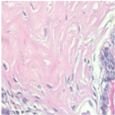

| Image Class | BreakHis Dataset(40×) | |||

| Benign | Malignant | |||

| Original images |  |  |  |  |

| MFF-ClassificationNet heatmaps |  |  |  |  |